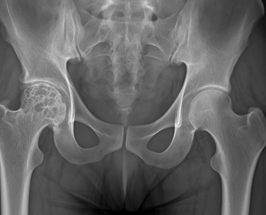

6. Necrosis avascular de la cabeza femoral

Es la pérdida de vitalidad del hueso de la cabeza del fémur debido a una disminución o interrupción de la circulación sanguínea. Puede aparecer tras fracturas de cadera, luxaciones, consumo prolongado de corticoides, alcoholismo o enfermedades sistémicas.

Síntomas principales:

- Dolor progresivo y persistente en la ingle, que puede irradiar al muslo o al glúteo.

- Con el tiempo se produce rigidez, limitación de movimientos (sobre todo rotación interna y flexión) y cojera evidente.

- Sin tratamiento, puede avanzar a una artrosis severa de cadera.